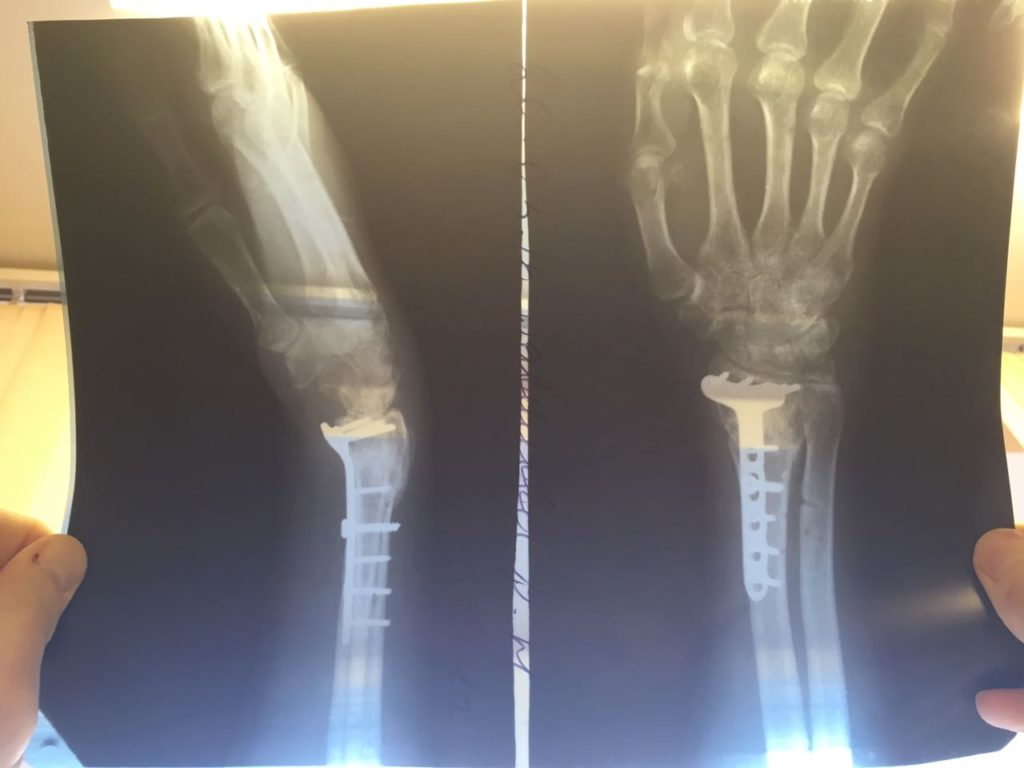

Операция - открытая репозиция, остеосинтез лучевой кости пластиной с костной ксенопластикой материалом "Остеоматрикс". На контрольных снимках в три месяца имеется консолидация перелома, миграции фиксатора нет, имеется остеоинтеграция ксенопластического материала.

Отдаленные результаты через 3 (три) месяца:

Отдаленные результаты через 6 (шесть) месяцев